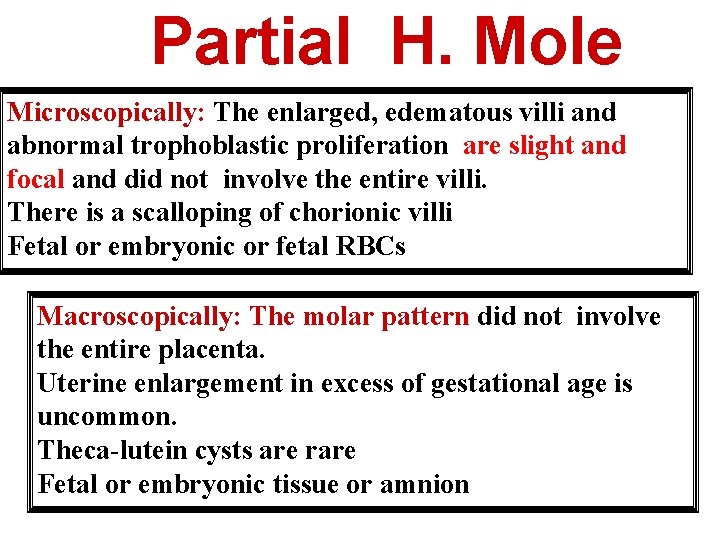

Partial H. Mole Microscopically: The enlarged, edematous villi and abnormal trophoblastic proliferation are slight and focal and did not involve the entire villi. There is a scalloping of chorionic villi Fetal or embryonic or fetal RBCs Macroscopically: The molar pattern did not involve the entire placenta. Uterine enlargement in excess of gestational age is uncommon. Theca-lutein cysts are rare Fetal or embryonic tissue or amnion

Partial Hydatidiform Mole Scalloping of chorionic villi Trophoblastic proliferation are slight and focal